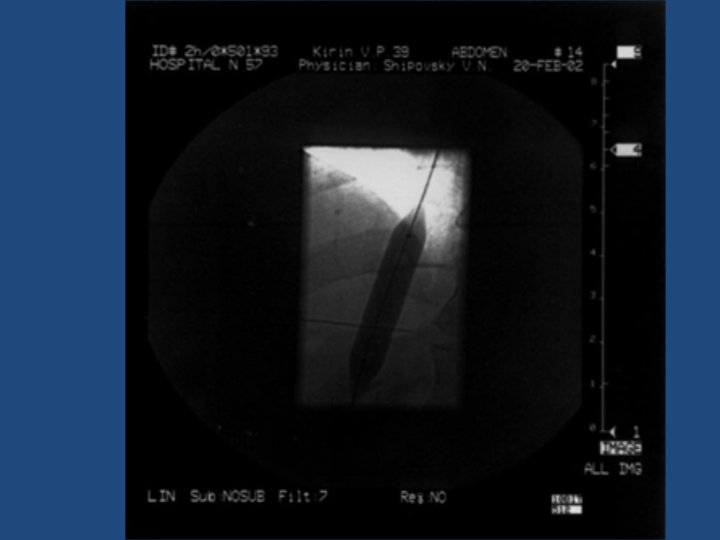

Результаты TIPS • • • Длительность процедуры 1 час до 3, 5 часов Повторные кровотечения – 10% Стеноз стента в течение двух лет – 20% Печеночная энцефалопатия Летальность 20% Максимальный срок наблюдения = 5 лет

Методика дистанционного обследования после TIPS • Клинический осмотр и лабораторные анализы • ЭГДС • Ультразвуковое дуплексное исследование портального кровотока • Ангиография ?